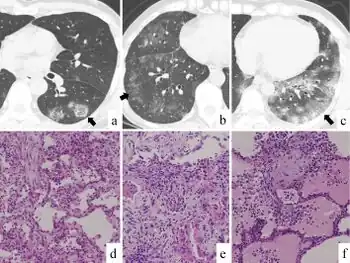

| a-f) Chest computed tomography and histologic findings of viral pneumonia | |